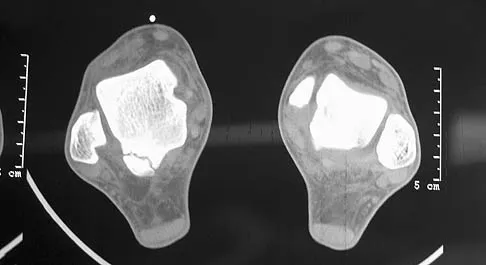

A 30-year-old man has had intermittent swelling of his right ankle for the past 6 months. He denies any history of trauma. Radiographs reveal osteolytic changes on both sides of the joint. An axial CT scan and a T2-weighted MRI scan are shown in Figures 40a and 40b. He undergoes surgical excision. An intraoperative photograph and a biopsy specimen are shown in Figures 40c and 40d. What is the most likely diagnosis?

Explanation

Pigmented villonodular synovitis often presents with intermittent swelling and minimal pain. It often occurs around joints but may be found around tendon sheaths and bursal linings. Periarticular erosions involving both sides of joints are typical, and multiple joint involvement has been described. Portions of low-signal intensity on T1- and T2-weighted images are characteristic of hemosiderin-laden processes. High-signal content is suggestive of high water content. The combination of low-signal intensity areas in intra-articular lesions with or without osseous destruction is diagnostic of pigmented villonodular synovitis. Aspiration reveals bloody or brownish fluid. The treatment of choice is synovectomy performed arthroscopically or open. Recurrence is common. Walling AK: Soft tissue and bone tumors, in Coughlin MJ, Mann RA (eds): Surgery of the Foot and Ankle, ed 7. St Louis, MO, Mosby, 1999, pp 1007-1032.